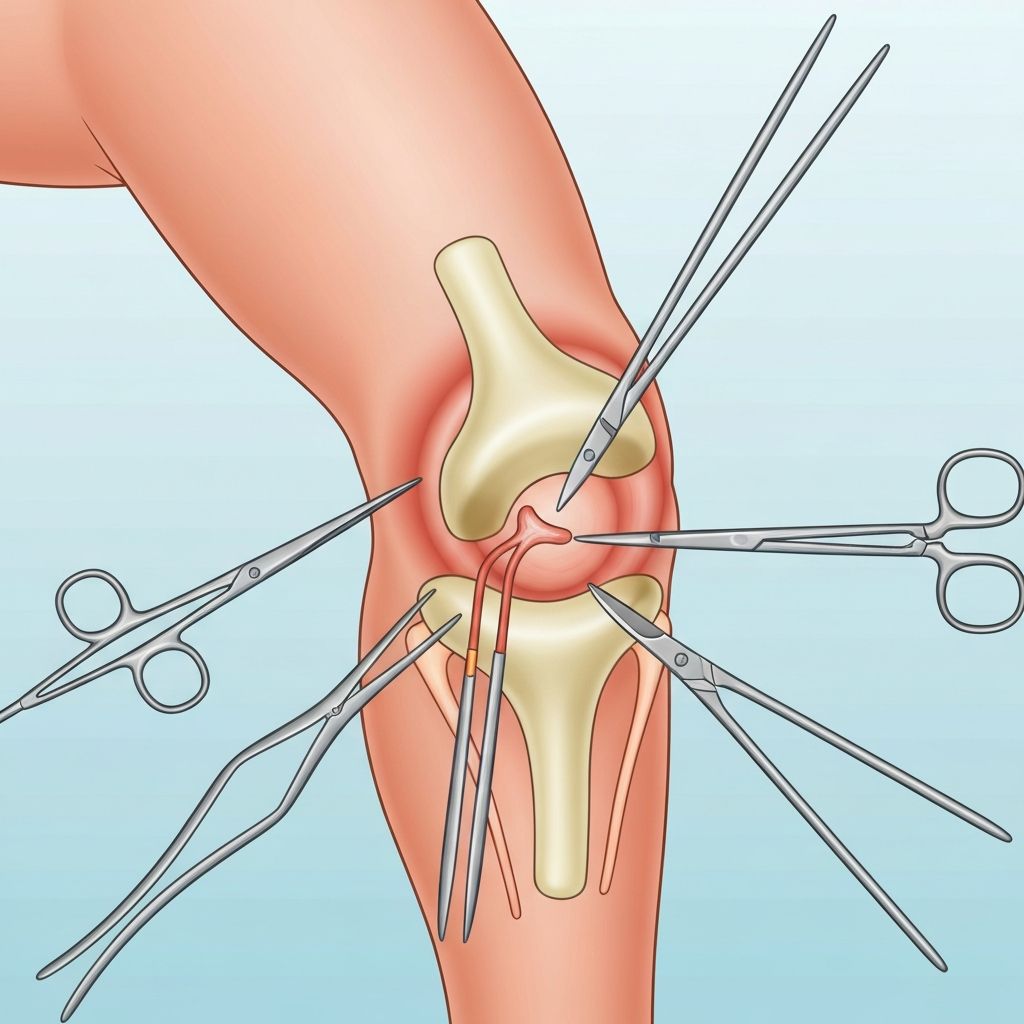

Orthopedic Surgery

Surgical treatment for bone, joint, and ligament conditions including fractures, arthritis, and degenerative diseases.

Joint Replacement

Advanced techniques for hip, knee, and shoulder replacement surgeries with excellent long-term outcomes.